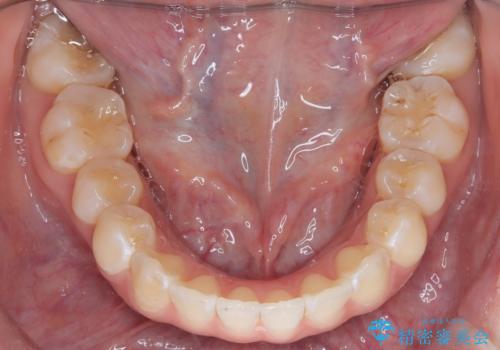

「フルリンガル矯正|アンカースクリューを活用し正中を整えた症例」

矯正装置を装着し、アンカースクリューを活用しながら奥歯を少しずつ後ろへ動かし、正中を整えていきました。治療には時間がかかりましたが、計画通りに歯を移動させ、バランスの取れた歯並びへと仕上げることができました。裏側矯正のため、見た目を気にすることなく治療を進められた点も、患者様にとって大きなメリットでした。治療後は、「正中がしっかり合って、口元がスッキリした」とご満足いただきました。